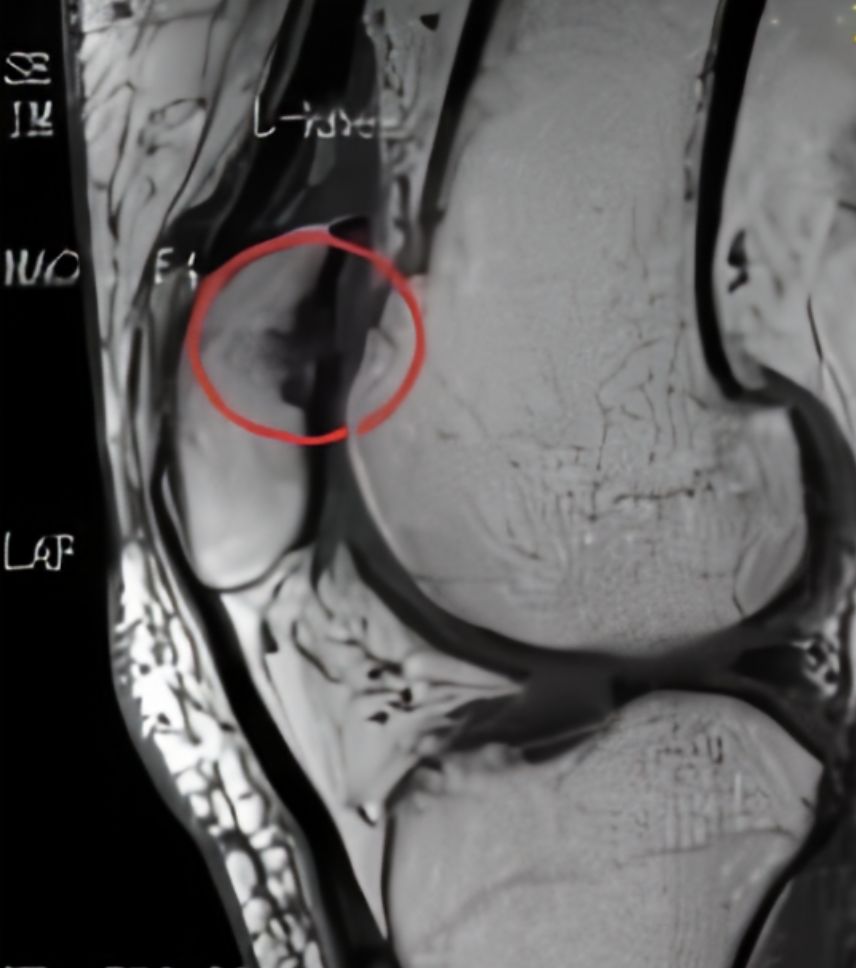

和“打软腿”相比,更严重的还是和膝关节其他部位发生不必要的接触和摩擦,关节受力也大大增加,长此以往,髌骨内侧就会磨损,这个过程被称为「髌骨软化」。表现为膝关节中心间歇性疼痛,下蹲和屈膝时会加重。单纯靠检查是很难区分出髌骨问题还是其他部位的问题,为了确诊,MRI是个直观的方法。

总是深蹲,髌骨内侧受力过大

通过MRI可以进一步观察膝关节软组织的炎症和肿胀程度,结合关节检查,可以更系统地了解到膝关节活动功能的异常在膝关节侧面的MRI片中,可以看到髌骨朝向膝关节的内侧表面软骨边缘有些毛糙,表示已经发生了一定程度的破坏,这些破坏来自于关节软骨之间的磨损,损伤严重的情况下还可以看到附近少量的关节积液。

髌骨软化实际上是关节面毛糙